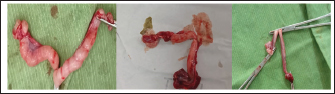

Fig. 1. The mammary lobes were extremely tight with asymmetrical swellings in two cases accompanied with ulcer in the 3rd one..

It was observed that the mammary lobes were extremely tight, and the size of the swollen mammary lobes ranged from 2 to 13 cm. Furthermore, the swellings were freely movable and did not adhere to the abdominal wall. Cats with FMH showed soft fluctuant jelly swelling in 32 cases (80%), asymmetrical swellings in 35 cases (87%) (Fig. 1), homogeneous swelling in 5 cats (12.5%), inflammation and edema in 15 cases (37.5%), dark color in 10 cases (25%), severe inflammation and bleeding in 4 cases (10%), necrosis in 4 cases (10%), abscess in 2 cases (5%), milk secretion in 17 cases (42.5%), and unwillingness to walk in 12 cases (30%) (Fig. 2).

Fig. 2. Showing severe swelling in the mammary lobes with edema in one case and sever ulcer and necrosis in the other case.

The mammary lobes were extremely tight, soft, fluctuant, jelly, asymmetrical, homogeneous, swollen, inflammatory, edema, dark color, severe inflammation, ulcerations with bleeding, necrosis, abscess, milk secretion, and unwilling to walk. Previous studies reported similar findings (Moulton, 1990; Rutteman and Withrow, 2001; Ginn et al., 2007; Payan, 2013). Most of these signs were attributed to the enlargement of the mammary lobe and exposure to trauma, causing ulceration and necrosis (Loretti et al., 2004; Voorwald et al., 2021). Fibroepithelial mammary hyperplasia was attributed to increased tissue volume, which led to perfusion problems, erythema, pain, ulceration, and dark and necrotic areas on the mammary gland skin (Bonatto et al., 2021; Voorwald et al., 2021).